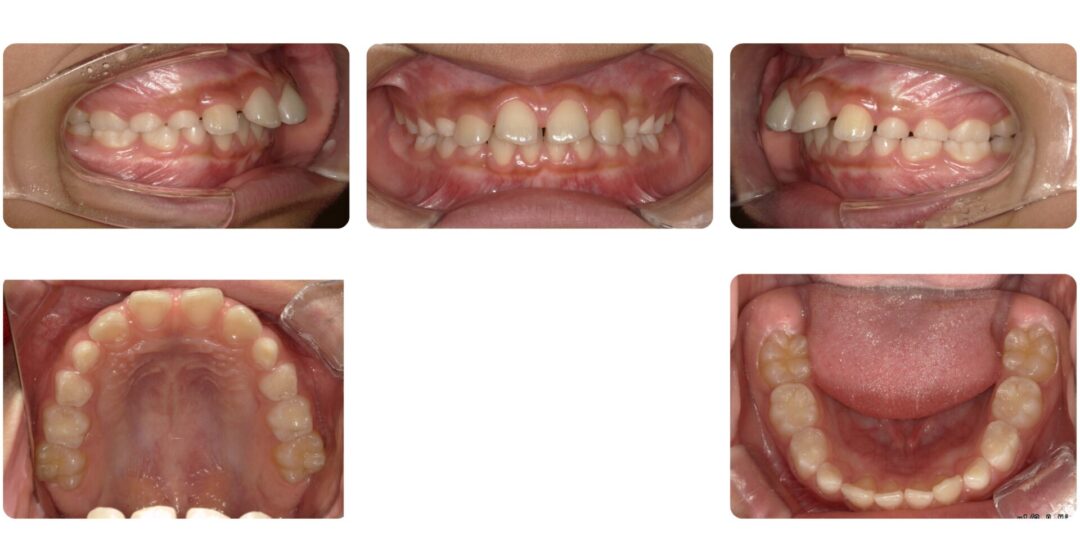

過蓋咬合を伴う骨格性上顎前突|初診時10歳

矯正治療後

治療内容

第一期治療 拡大ネジ付きバイオネーターによる歯列矯正

治療期間

1年5ヶ月